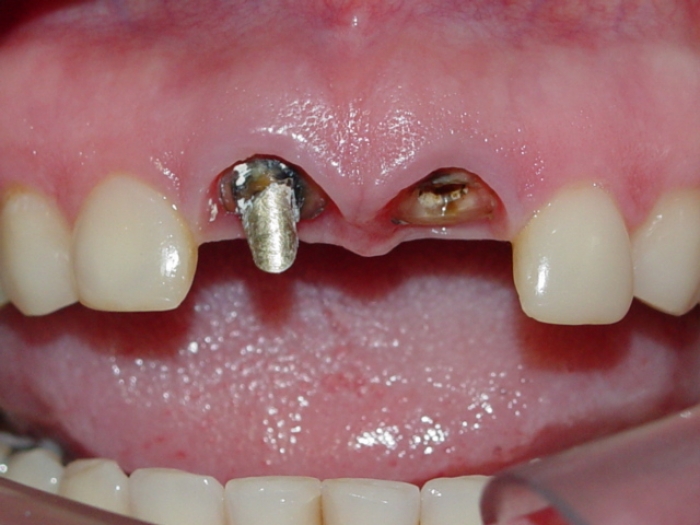

Prótese fixa em porcelana sobre implante Cone Morse